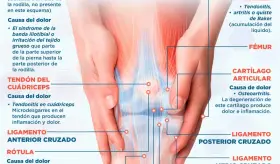

#InfografíaMSP El uso frecuente de tacones altos altera la postura, sobrecarga el antepié y afecta desde los pies hasta la columna vertebral, aumentando el riesgo de juanetes, dolor muscular y desgaste articular.